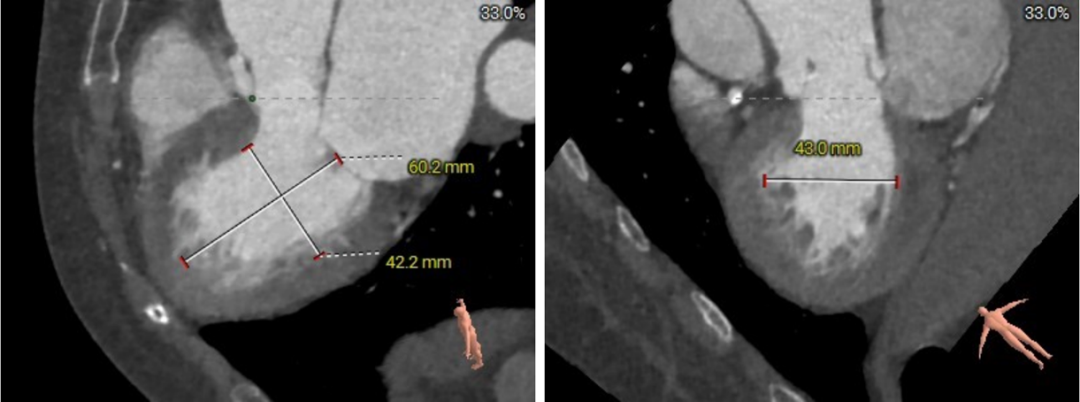

主动脉根部评估

四叶式主动脉瓣,右无间窦体发育较小且窦底高于瓣环平面约6mm;

AAO轻度扩张,Max>43.1;

瓣环上结构测量

收缩期瓣上结构

收缩期瓣上可提供4~6mm筒状区域。

舒张期瓣上结构

舒张期瓣上5mm内区域均小于收缩瓣环径;

该病例的瓣上结构可提供的辅助锚定区域较长,有利于瓣膜的辅助锚定。

流出道结构测量

收缩期流出道结构

收缩期流出道可提供6mm筒状区域。

舒张期流出道结构

舒张期流出道约3mm筒状区域;

流出道收缩期和舒张期可锚定区域波动较大,整体约4mm辅助锚定区域。

冠脉高度、瓣叶长度及左室内径

左冠高度:7.1mm;右冠高度:13.4mm;

左冠-窦底距:9.7mm;右冠-窦底距:14.4mm;

左冠瓣长度:12.3mm;右冠瓣长度:14.8mm;

左冠水平高度较低,开口内径较大,瓣叶略长,LCC至对合缘距离约30mm,存在一定左冠阻塞风险。

左室室间隔基底部肌性凸起,增加了流出道锚定有利因素。